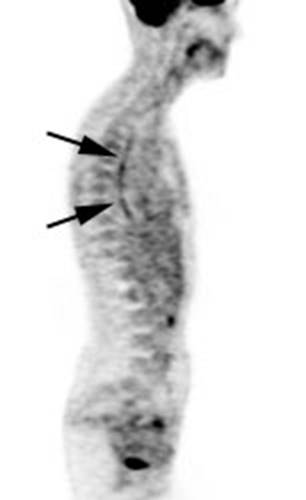

Figure 17 - Segmental colon activity in

diverticular disease:

Note the segmental FDG uptake corresponding to an area of severe diverticular

disease on CT. There is likely underlying inflammation or muscular spasm which

contributes to the FDG uptake

Figure 18 - Gastric activity: Gastric activity can be

very intense- even in patients without gastrointestinal disease. Note the

"ring-like" appearance of normal gastric activity.

Figure 19 - Esophageal activity: The image below

demonstrates non-specific esophageal activity which appears as linear uptake

anterior to the spine (black arrows).

Figure 20 - Ostomy sites: Tracer uptake at ostomy

sites is common